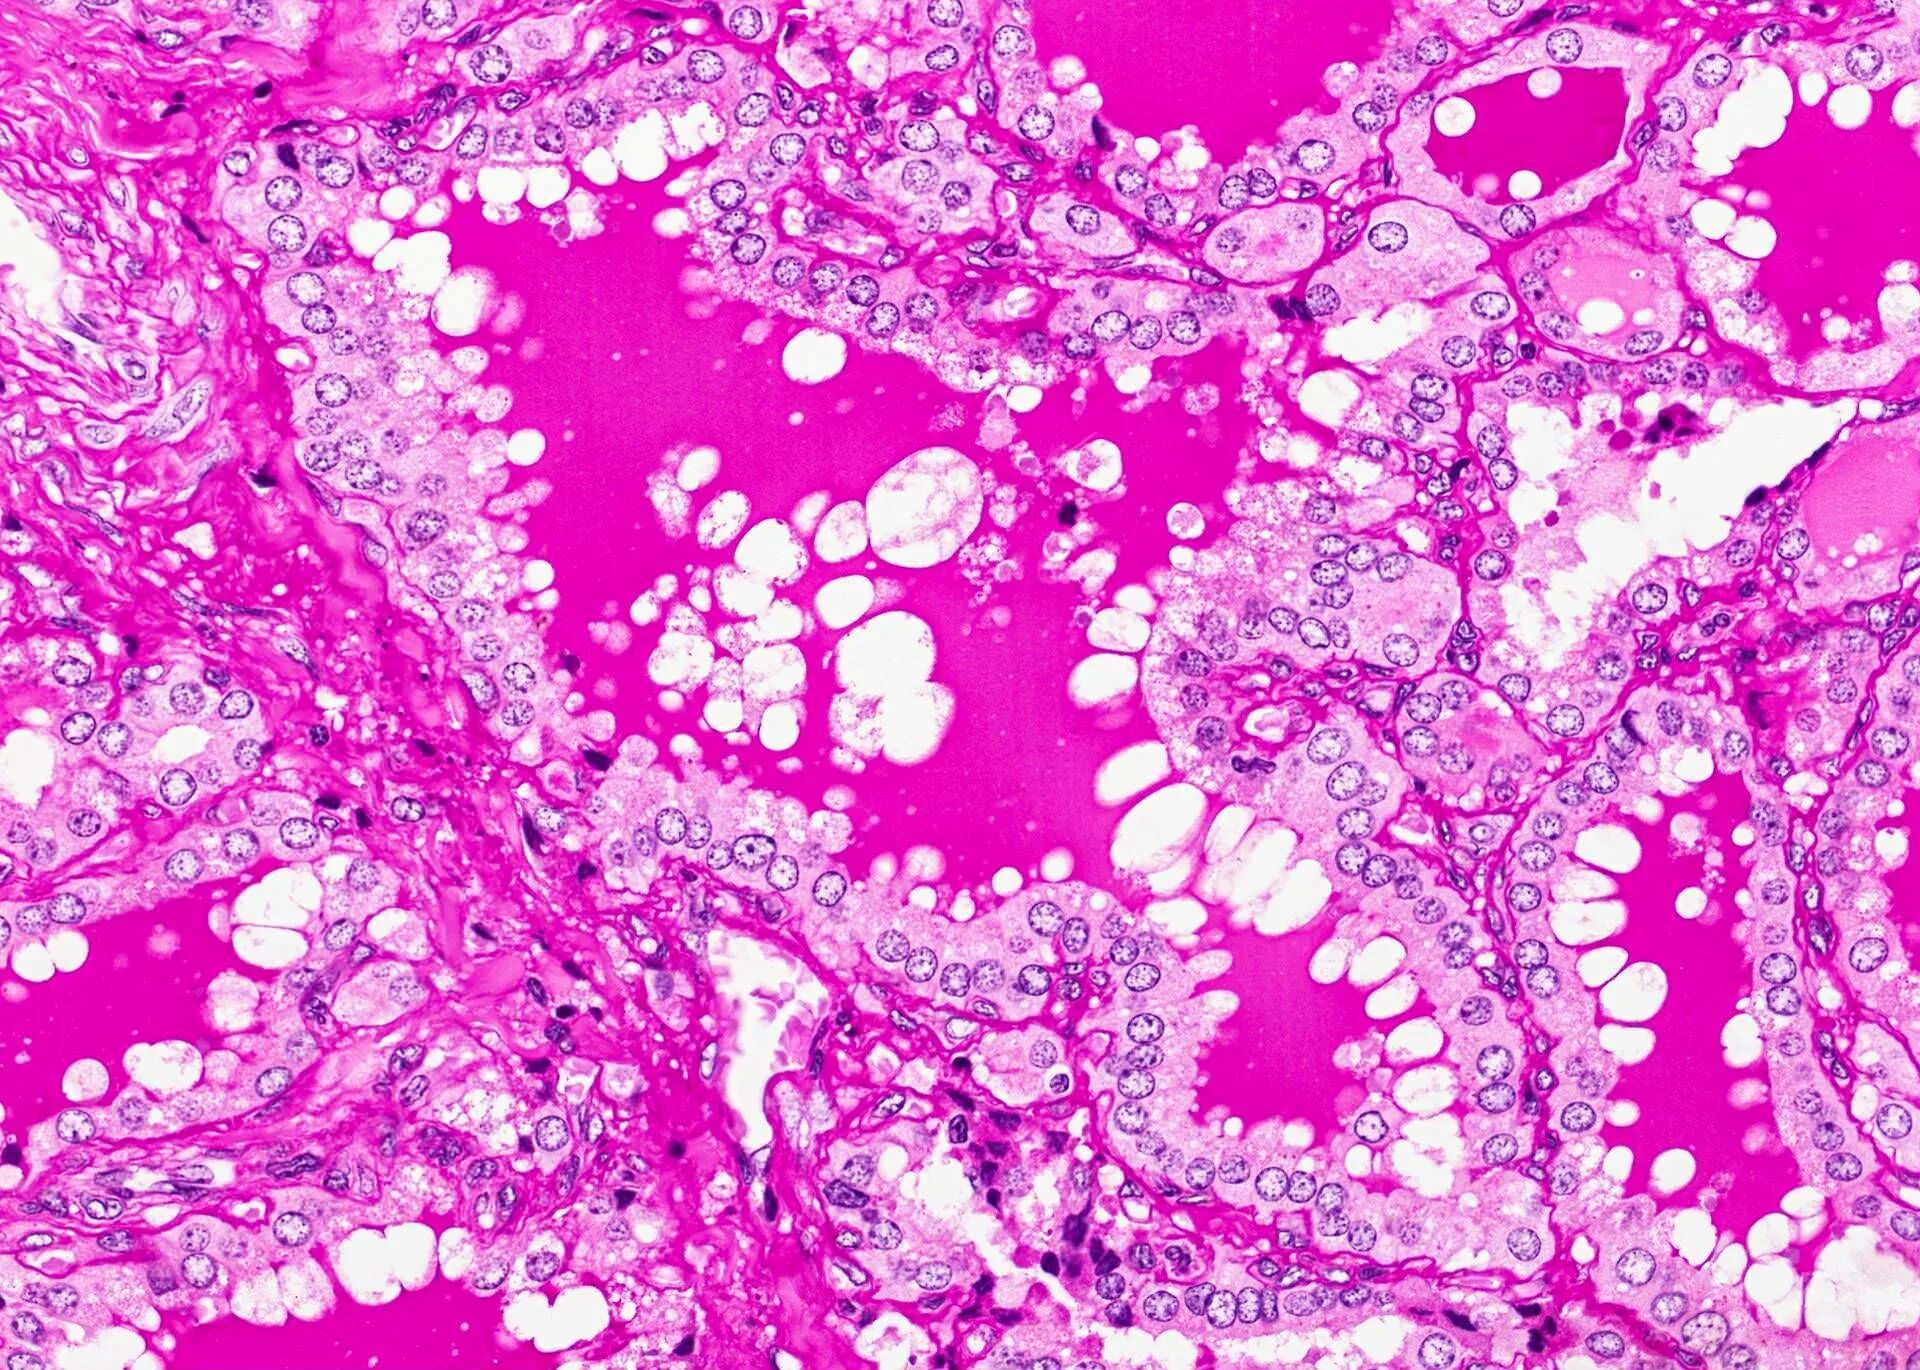

Гистология смешанный